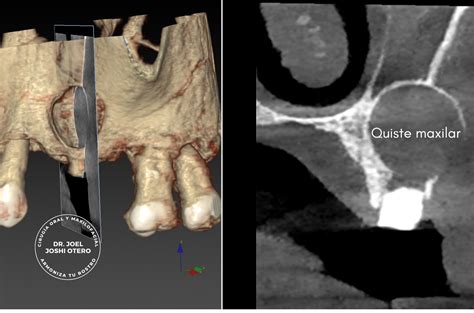

Algunos quistes tienen una causa genética. Entre ellos están los relacionados con el desarrollo de los maxilares y los dientes en edades tempranas. Otros quistes derivan de caries profundas que han llegado al nervio. En la imagen de la portada (corte de un TAC en 3D) se observa un quiste naso-palatino, uno de los más comunes de la cavidad oral.

Tal y como muestra la imagen anterior, los senos maxilares son las cavidades que conforman los senos nasales de la cara. Son cavidades grandes y tienen forma piramidal. Los senos maxilares están ubicados uno a cada lado de la cara.

Generalmente es necesario realizar una radiografía para diagnosticar esta patología que se manifiesta a través de una zona oscura en el hueso. En la ortopantomografía (radiografía en 2D de toda la boca) el quiste maxilar se observa como una zona oscura y redondeada en forma de bolsa.

El principal método para detectar un quiste maxilar es a través de una radiografía, en la que se puede observar una mancha de color oscuro en el hueso. Una vez que el dentista sepa de la presencia del quiste, es posible que solicite pruebas adicionales, tales como una tomografía computarizada o una biopsia, que le permitan tener una información más completa y detallada sobre el tipo de quiste, la extensión del mismo y sus características.